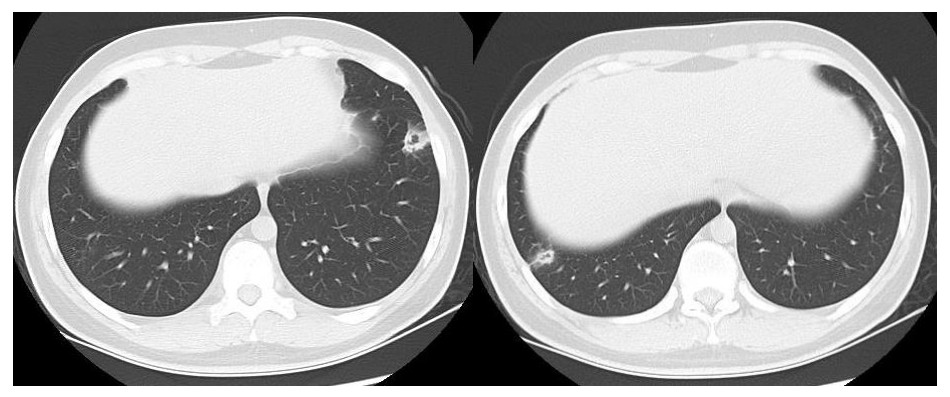

患者男性,21岁,主因“间断发热、寒战伴头晕头痛2周”于2021年11月18日急诊收入院。患者诉2周前进食烧烤后出现发热,体温最高可达42℃, 伴畏寒、寒战、咽痛、头晕、头痛、乏力,就诊于本院耳鼻喉科后,查体见扁桃体有脓点,快测降钙素原(procalcitonin,PCT)为37.27 ng/mL,胸部CT检查未见异常,考虑诊断为“急性化脓性扁桃体炎”,先后给予左氧氟沙星、阿奇霉素抗感染及甲泼尼龙控制炎症后上述症状未见明显好转,为进一步治疗,收入急诊病房治疗,既往体健,入院时查体:体温41℃,脉搏98次/min,呼吸频率23次/min,血压120/60 mmHg(1 mmHg=0.133 kPa),患者神志清楚,急性病容,精神较差,颈部浅表淋巴结触及肿大,右侧较大约2.0 cm ×0.5 cm,左侧较大约1.3 cm×0.7 cm,质软,活动度好,界限清楚,有压痛,表面皮肤无红肿,无破溃,双肺呼吸音清,未闻及干湿性啰音,心脏听诊无杂音,腹软,无压痛及反跳痛,双下肢无水肿。血常规检查白细胞计数10.49×109/L, 中性粒细胞百分比94.6%,血红蛋白120 g/L, 血小板计数107×109/L,PCT 42.83 ng/mL,白介素6(interleukin, IL-6)980.30 pg/mL,C反应蛋白211 mg/L,G试验、GM试验阴性。胸部CT检查示右肺上叶可见一单发实变影,其内可见空洞(图 1)。根据病史、查体和辅助检查考虑诊断为肺脓肿,给予注射用哌拉西林钠他唑巴坦4.5 g Q8h治疗,入院第2天,患者仍有发热,体温最高38.7℃,给予对症处理,入院第3天患者体温峰值有所下降,体温维持在37~38℃,考虑抗炎有效,痰培养结果回报为纹带棒杆菌,草绿色链球菌(奈瑟菌属),考虑这2种细菌为皮肤或口腔的正常菌群,为条件致病菌,该细菌导致发热的可能性较小,继续给予哌拉西林钠他唑巴坦治疗。入院第5天血培养回报血液中找到坏死梭杆菌,考虑为血流感染。加用甲硝唑1 g每8 h一次抗感染治疗,复查血常规白细胞计数8.14×109/L, 中性粒细胞百分比81.5%,血红蛋白120 g/L, 血小板计数246×109/L,PCT 3.43 ng/mL,IL-6 13.04 pg/mL,C反应蛋白5 mg/L,炎性指标较前明显下降,考虑抗炎治疗有效,继续目前抗生素治疗。入院第10天患者体温仍有低热,体温36.5~37.5 ℃,复查胸部CT见双肺多发小结节,双肺多发空洞病变,考虑炎性可能(图 2)。颈静脉超声检查提示患者左侧颈内静脉血栓形成,给予依诺肝素0.4 mL每12 h一次抗凝治疗,根据血培养结果、胸部CT表现和颈静脉超声结果,考虑该患者诊断为坏死梭杆菌导致Lemierre综合征(Lemierre syndrome, LS)。用哌拉西林钠他唑巴坦联合甲硝唑治疗后仍有低热,化验检查PCT为0.30 ng/mL,IL-6为3.52 pg/mL,C反应蛋白为3 mg/L,胸部CT示肺部空洞较前增加,考虑感染未完全控制,改为调整抗生素为比阿培南0.6 g每12 h一次联合甲硝唑1g每8 h一次抗感染治疗,治疗1周后患者体温恢复正常,CT检查示双肺多发空洞消失,残留少量索条影(图 3),患者病情好转出院,出院带药给予口服甲硝唑联合阿莫西林抗感染治疗,利伐沙班抗凝治疗,随诊2周后复查胸部CT正常。

| 右肺上叶可见一单发实变影,其内可见空洞 图 1 入院时胸部CT |

LS的致病菌主要为坏死梭杆菌,因此LS也被称为坏死梭杆菌病,其他致病菌包括核杆菌、类杆菌、链球菌和葡萄球菌等[5]。坏死梭杆菌为厌氧革兰阴性多形态杆菌,广泛存在于人类和动物的口腔、上呼吸道、胃肠道和泌尿生殖道的正常菌群。坏死梭杆菌可以产生白细胞毒素、内毒素、溶血素和血细胞凝集素等,白细胞毒素和溶血素与脓肿形成相关,血细胞血凝素可引起动静脉血栓形成,可导致转移性脓肿,弥漫性血管内凝血和血小板减少也与此有关[6]。患者起初为咽部感染,然后通过咽旁间隙侵袭至颈内静脉,形成颈内静脉血栓,脓毒性栓子随着血流播散至肺部,引起肺部脓肿和肺栓塞。本例患者刚发热时胸部CT正常,门诊给予喹诺酮类药物和大环内酯类药物治疗2周后,入院时胸部CT示患者右肺中叶单发实变影,其内可见空洞样变,后随病情发展,胸部CT示双肺多发肺空洞样变,符合LS的临床表现。LS最初表现为喉咙痛或颈部疼痛, 但可出现多种非特异性症状, 如全身僵硬、寒战、发热、颈部淋巴结肿大、眼眶疼痛、骨/关节疼痛、四肢无力、恶心、呕吐等胃肠道症状。最初感染1周后,可以在血液中找到细菌,然后在颈静脉内脓毒性血栓形成,可以肺内形成肺脓肿和脓胸,也可以累及关节[7]。